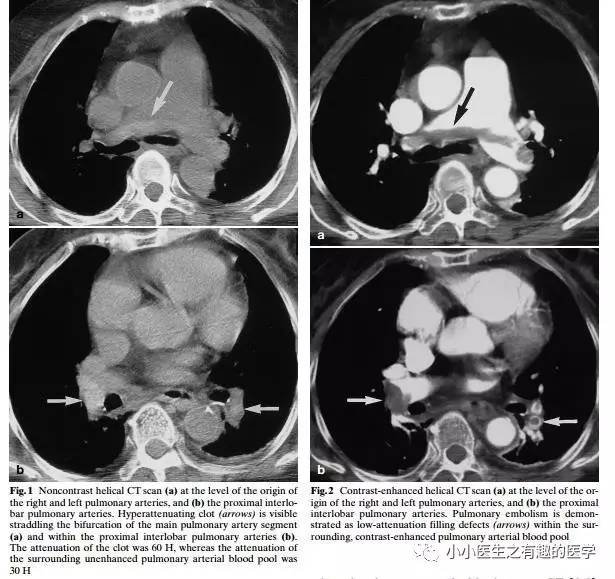

国外有高手专门研究了CT平扫诊断肺栓塞的可靠程度。

高分辨CT平扫管腔内高密度征象诊断肺栓塞的敏感性36.0%, 特异性99.0%, 阳性预测值90.0%, 阴性预测值85.6% 。

阴沟里洗原文:The hyperdense lumen sign has an over-all sensitivity of 36.0%, specificity of 99.0%, PPV of 90.0%, and NPV of 85.6% (κ = 0.449; P-value < 0.001).

高分辨CT平扫管腔内高密度征象诊断中心肺栓塞敏感性66.7%, 特异性99.1%。

阴沟里洗原文: In detecting central thromboembolism, the sensitivity, specificity, PPV, and NPV of this sign were 66.7, 99.1, 88.9, and 96.4%, respectively (κ = 0.740; P-value < 0.001).